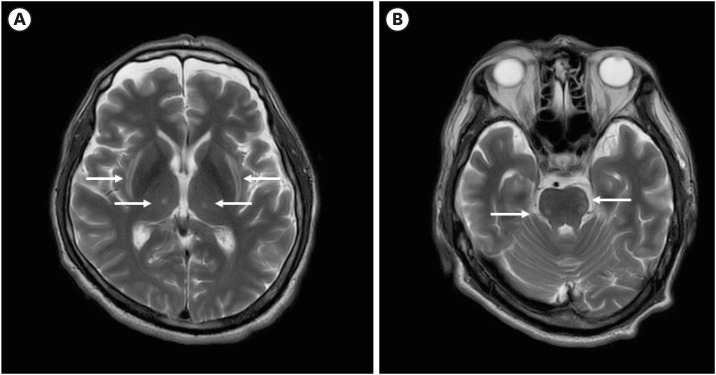

渗透性脱髓鞘综合征(ODS)是一种罕见的神经系统疾病与渗透失衡。传统上,已知ODS发生在低钠血症快速纠正之后;然而,ODS也被报道与高钠血症和高血糖有关。胼胝体细胞毒性病变(CLOCC)可由多种原因引起,包括药物、血管疾病、感染和代谢紊乱,如电解质失衡和血糖异常。ODS和CLOCC同时发生的情况极为罕见。在这里,我们报告了一例57岁男性,最初通过严重高钠血症和高渗性高血糖状态(HHS)发展为CLOCC,随后也被确定为ODS。医生应该知道CLOCC可能是与严重高钠血症和HHS相关的ODS的早期放射学发现。因此,在这些患者中应考虑积极的脑成像,以促进早期发现神经系统并发症。

Osmotic demyelination syndrome (ODS) is a rare neurological disorder associated with osmotic imbalances. Traditionally, ODS has been known to occur following the rapid correction of hyponatremia; however, ODS has also been reported concerning hypernatremia and hyperglycemia. Cytotoxic lesions of the corpus callosum (CLOCC), identified using transient magnetic resonance imaging, can arise from various causes, including drugs, vascular diseases, infections, and metabolic disturbances such as electrolyte imbalances and dysglycemia. The simultaneous occurrence of ODS and CLOCC is extremely rare. Here, we report a case whereby a 57-year-old male initially developed CLOCC via severe hypernatremia and hyperosmolar hyperglycemic state (HHS) was also subsequently identified with ODS. Physicians should know CLOCC may be an early radiologic finding in ODS associated with severe hypernatremia and HHS. Therefore, proactive brain imaging should be considered in these patients to facilitate the early detection of neurological complications.